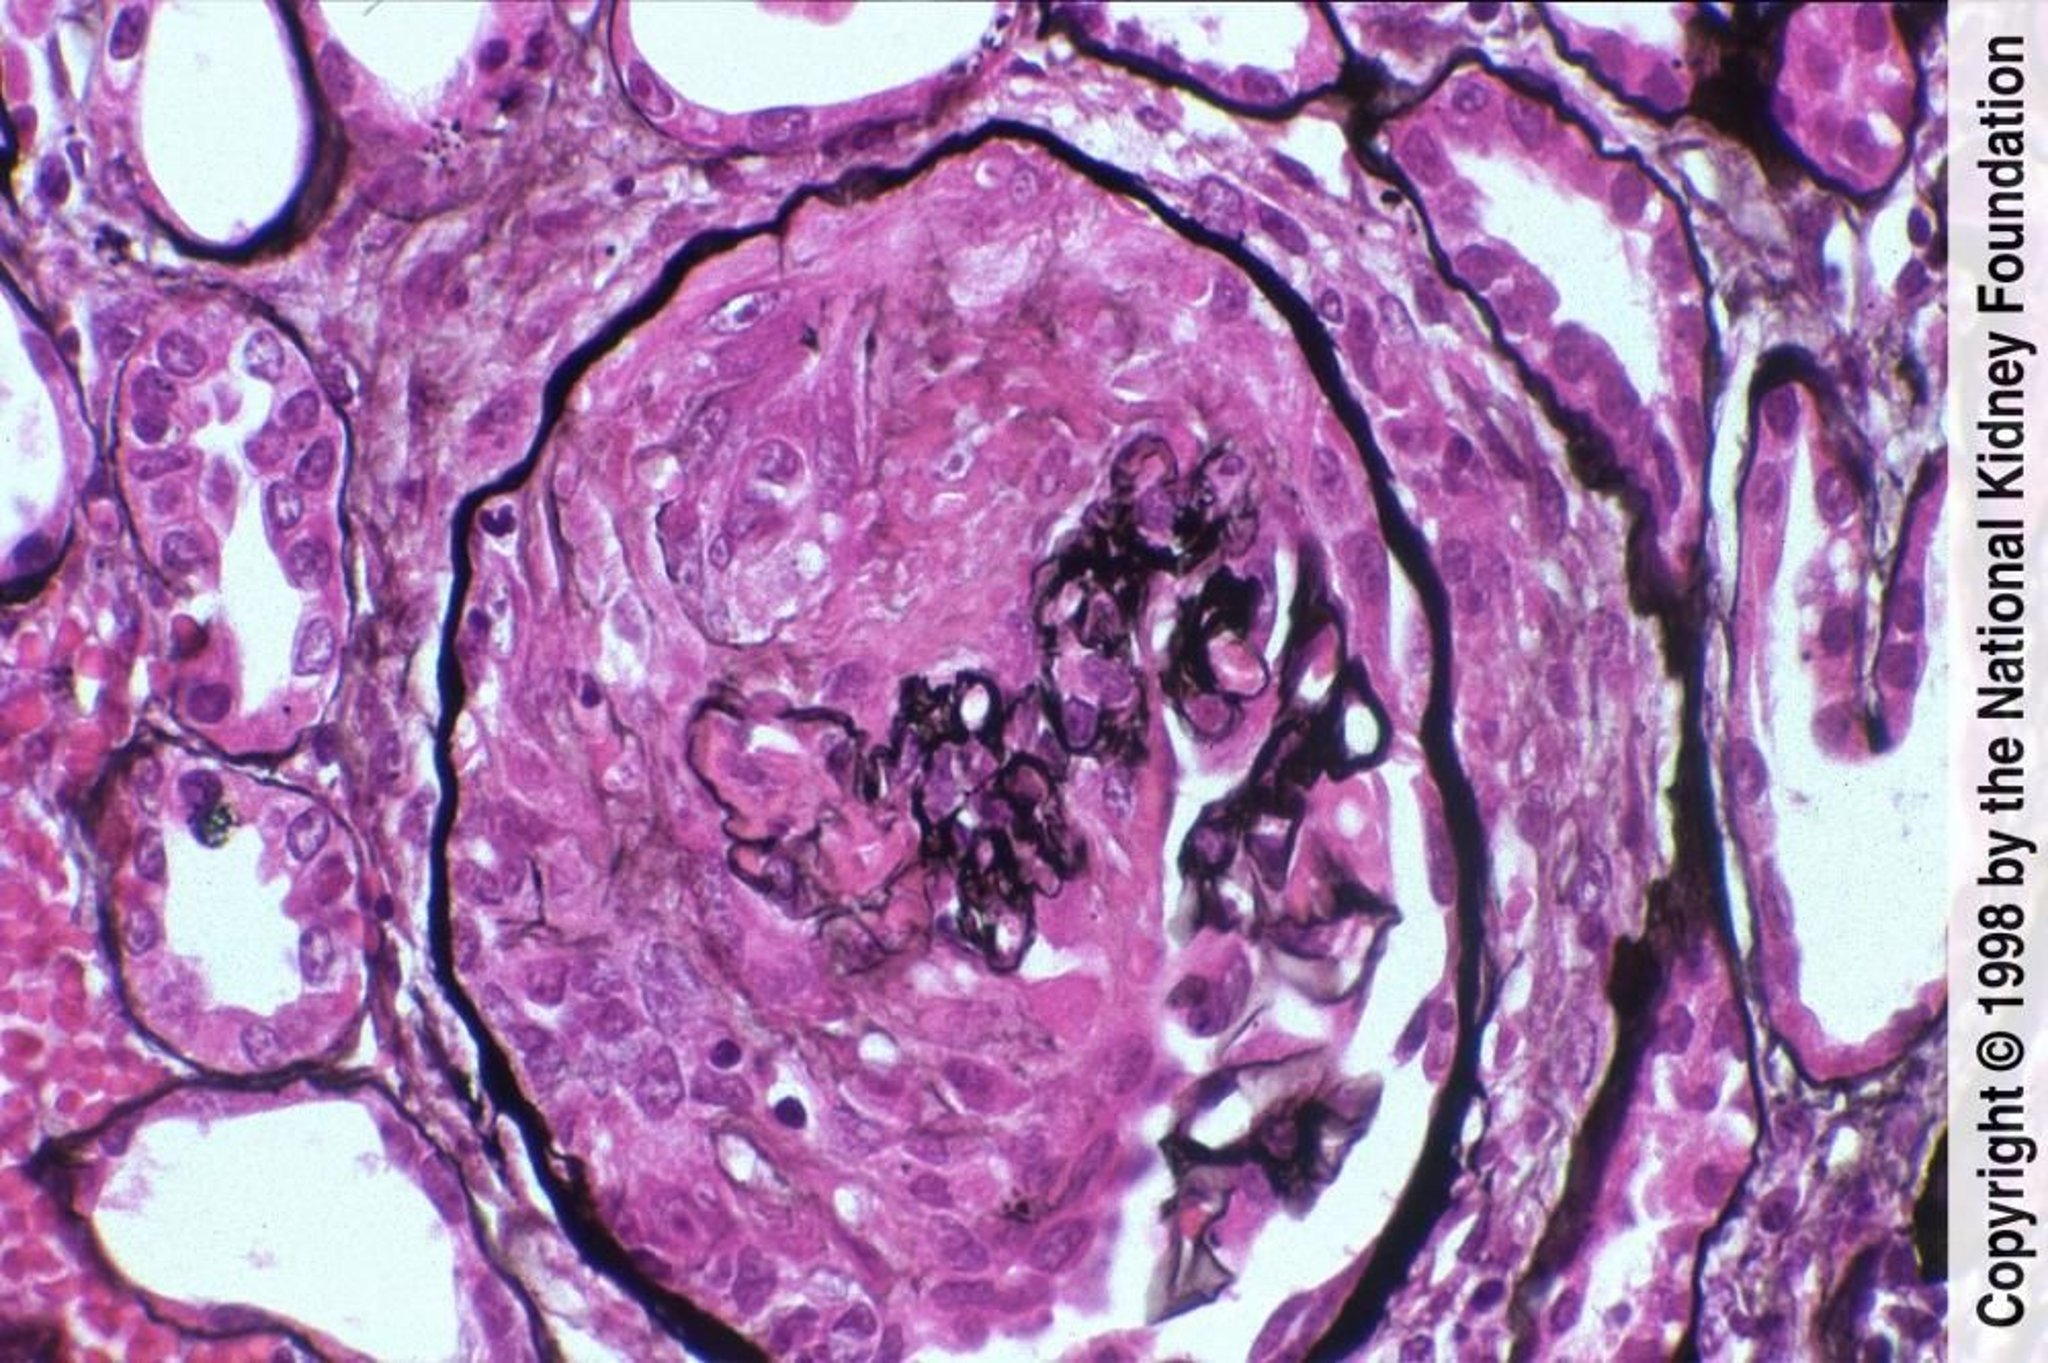

Glomerulonefrite rapidamente progressiva (pauci-Immune)

La glomerulonefrite pauci-immune è caratterizzata dalla formazione di semilune con necrosi fibrinoide e colorazione negativa in immunofluorescenza (colorazione all'argento di Jones, ×400).

Imagine fornita da Agnes Fogo, MD, and the American Journal of Kidney Diseases' Atlas of Renal Pathology (vedi www.ajkd.org).